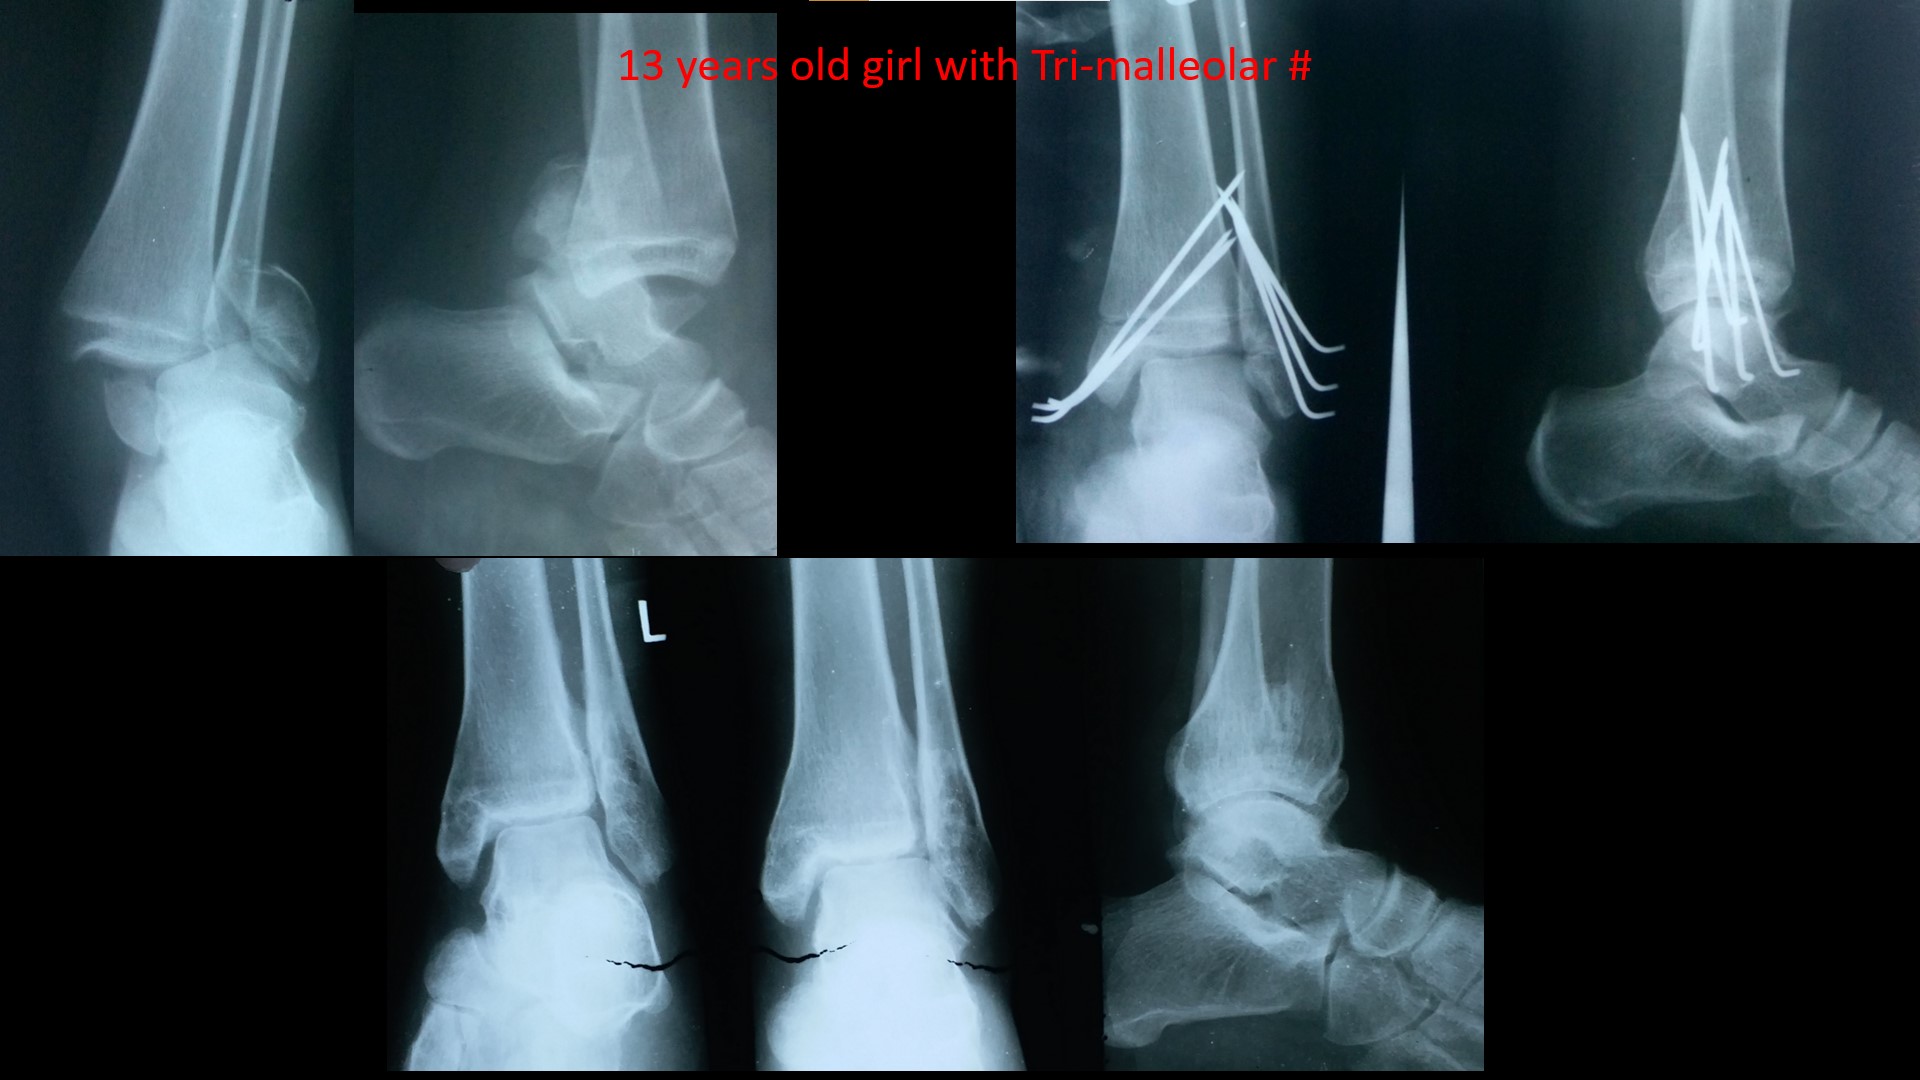

ANKLE